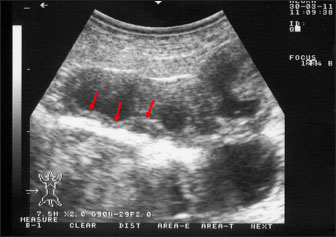

Ultrasonography has been proven effective for the early detection of several abdominal and thoracic disorders in small ruminants (Tharwat et al., 2012b; Tharwat and Al-Sobayil, 2017; Tharwat, 2021; Sadan et al., 2023; Tharwat and Al-Hawas, 2024a,b; Tharwat et al., 2024; Tharwat et al., 2025b). Recently, the technique has been found valuable for the diagnosis of various bacterial and parasitic infections in ruminants (Tharwat and Tsuka, 2024). An overall increase in intestinal mucosa thickness was detected in goats with PTB. It was classified as either mild, moderate, or severe (Fig. 2). Corrugation and folding of the intestinal mucosa may be also imaged in goats with PTB (Fig. 3). However, remarkable enlargement of the mesenteric lymph nodes are the most important findings in goats with PTB (Fig. 4). Other sonographic changes included increased hepatic brightness, intestinal edema consolidated lungs, and pleural, peritoneal, and pericardial effusions (Tharwat et al., 2012b).

Fig. 2. Ultrasonography of the thickened intestinal walls in a goat with paratuberculosis. Thickening of the intestinal mucosa is apparent cross sectionally (red arrows).